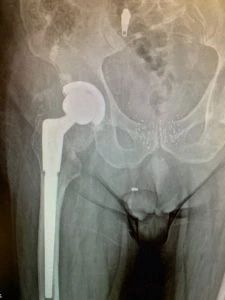

Plain film radiographs revealed thinning and “penciling” of the neck of the femoral component, indicating likely fretting corrosion at the trunion – also known as “trunnionosis”. In fact the radiographs suggested the trunion had become so corroded that it had fractured. Further inquiry revealed the type of component used in the initial replacement surgery has since been shown to suffer from this phenomenon at a higher rate than others – though this was not known at the time.

We carefully removed the femoral component and the plastic liner of the acetabular component – testing of the metal shell revealed it to be stable so it was decided this part of the original procedure would remain intact. We prepared and inserted the revision femoral component without event and trialed femoral head components with trial acetabular liner components to ensure the hip remained stable. Once we were satisfied with our component sizes, definitive components were placed and the procedure was completed.

6 weeks following surgery, Mr. JF had recovered most of his strength, had been returned to his former pain-free status and has not had any recurrent episodes or feelings of instability to date.